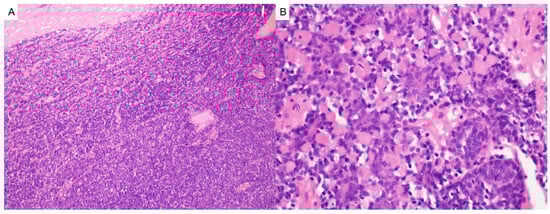

Neurofibromas

- Gerber, P.A.; Antal, A.S.; Neumann, N.J.; Homey, B.; Matuschek, C.; Peiper, M.; Budach, W.; Bölke, E. Neurofibromatosis. Eur. J. Med. Res. 2009, 14, 102–105. [Google Scholar] [CrossRef] [PubMed]

- Ortonne, N.; Wolkenstein, P.; Blakeley, J.O.; Korf, B.; Plotkin, S.R.; Riccardi, V.M.; Miller, D.C.; Huson, S.; Peltonen, J.; Rosenberg, A.; et al. Cutaneous neurofibromas: Current clinical and pathologic issues. Neurology. 2018, 91 (Suppl. 1), S5–S13. [Google Scholar] [CrossRef]

- Poplausky, D.; Young, J.N.; Tai, H.; Rivera-Oyola, R.; Gulati, N.; Brown, R.M. Dermatologic Manifestations of Neurofibromatosis Type 1 and Emerging Treatments. Cancers 2023, 15, 2770. [Google Scholar] [CrossRef] [PubMed]